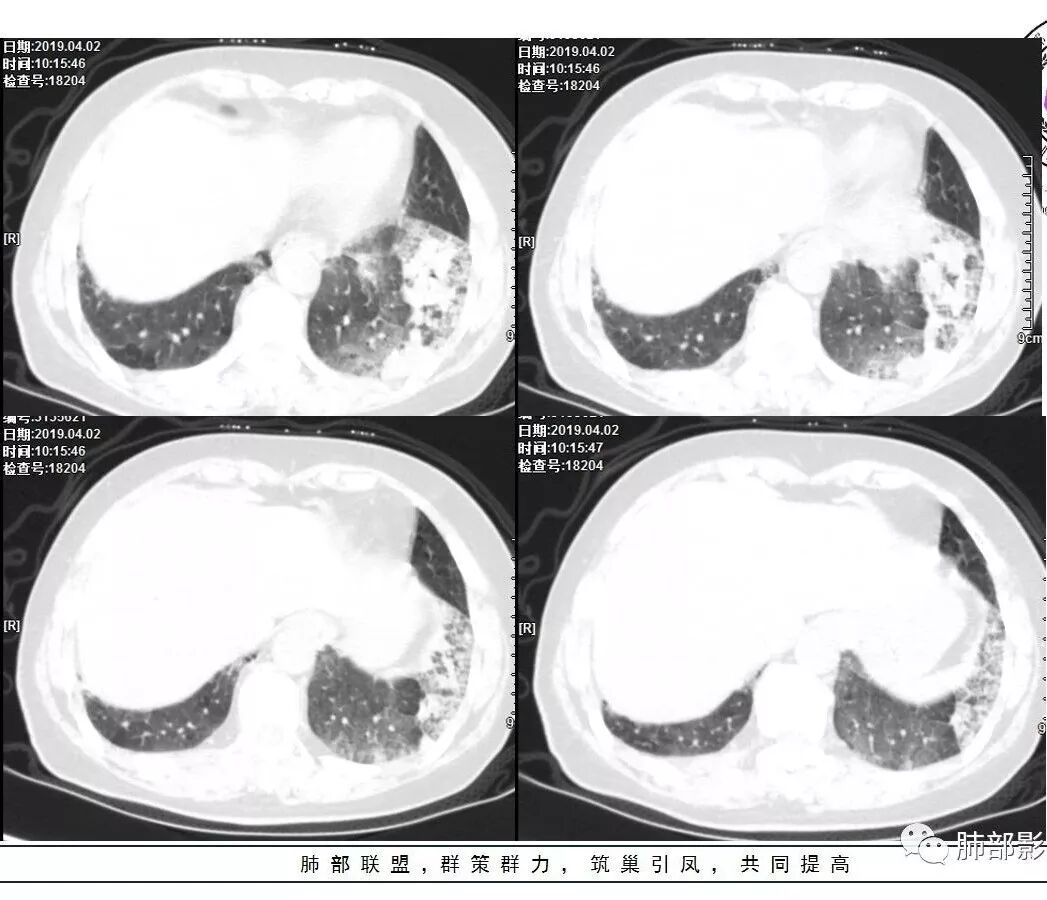

胸CT:左下叶基底段支气管狭窄,沿支气管分布斑片实变影、网格影、磨玻璃影,支气管充气征,无重力效应,左肺门淋巴结肿大、钙化。

2.左肺下叶片状影及多数有边界的结节影,较散,多形性,密度不均(注意许多老师提到这个特点还是比较明显的)。左肺下叶体积未见缩小。

3.病灶强化比较明显。

4.左下叶支气管壁增厚,管腔不均匀狭窄,没有堵塞

5.肺门纵隔见增大钙化淋巴结。提示曾经存在慢性病损可能。

1.前述特点除强化外都还是很容易让人首先想到肺结核的可能性。结核是常见病。注意肉芽肿明显的结核灶可以观察到强化。

2.淀粉样变性病变支气管改变一般会更广泛,较少出现单叶肺的如此大片影。

3.腺癌不大会出现较散的腺泡样结节影,更不会出现如本例的支气管改变。增大钙化的淋巴结也很难相互关联。

4.相关支气管未见腔内结节及阻塞,女性患者,鳞癌的可能性更小。